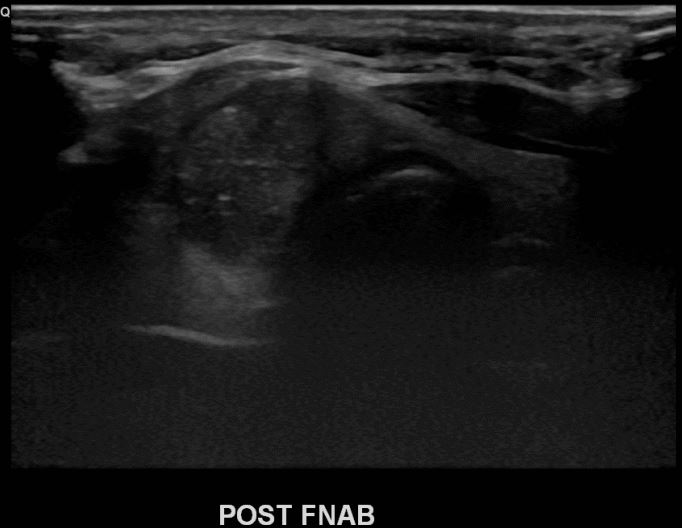

상기환자 목이튀어나와 내원하신 20대후반 여성분으로 의심스러운 우엽혹 세포검사진행후 갑상선암으로 진단되었습니다